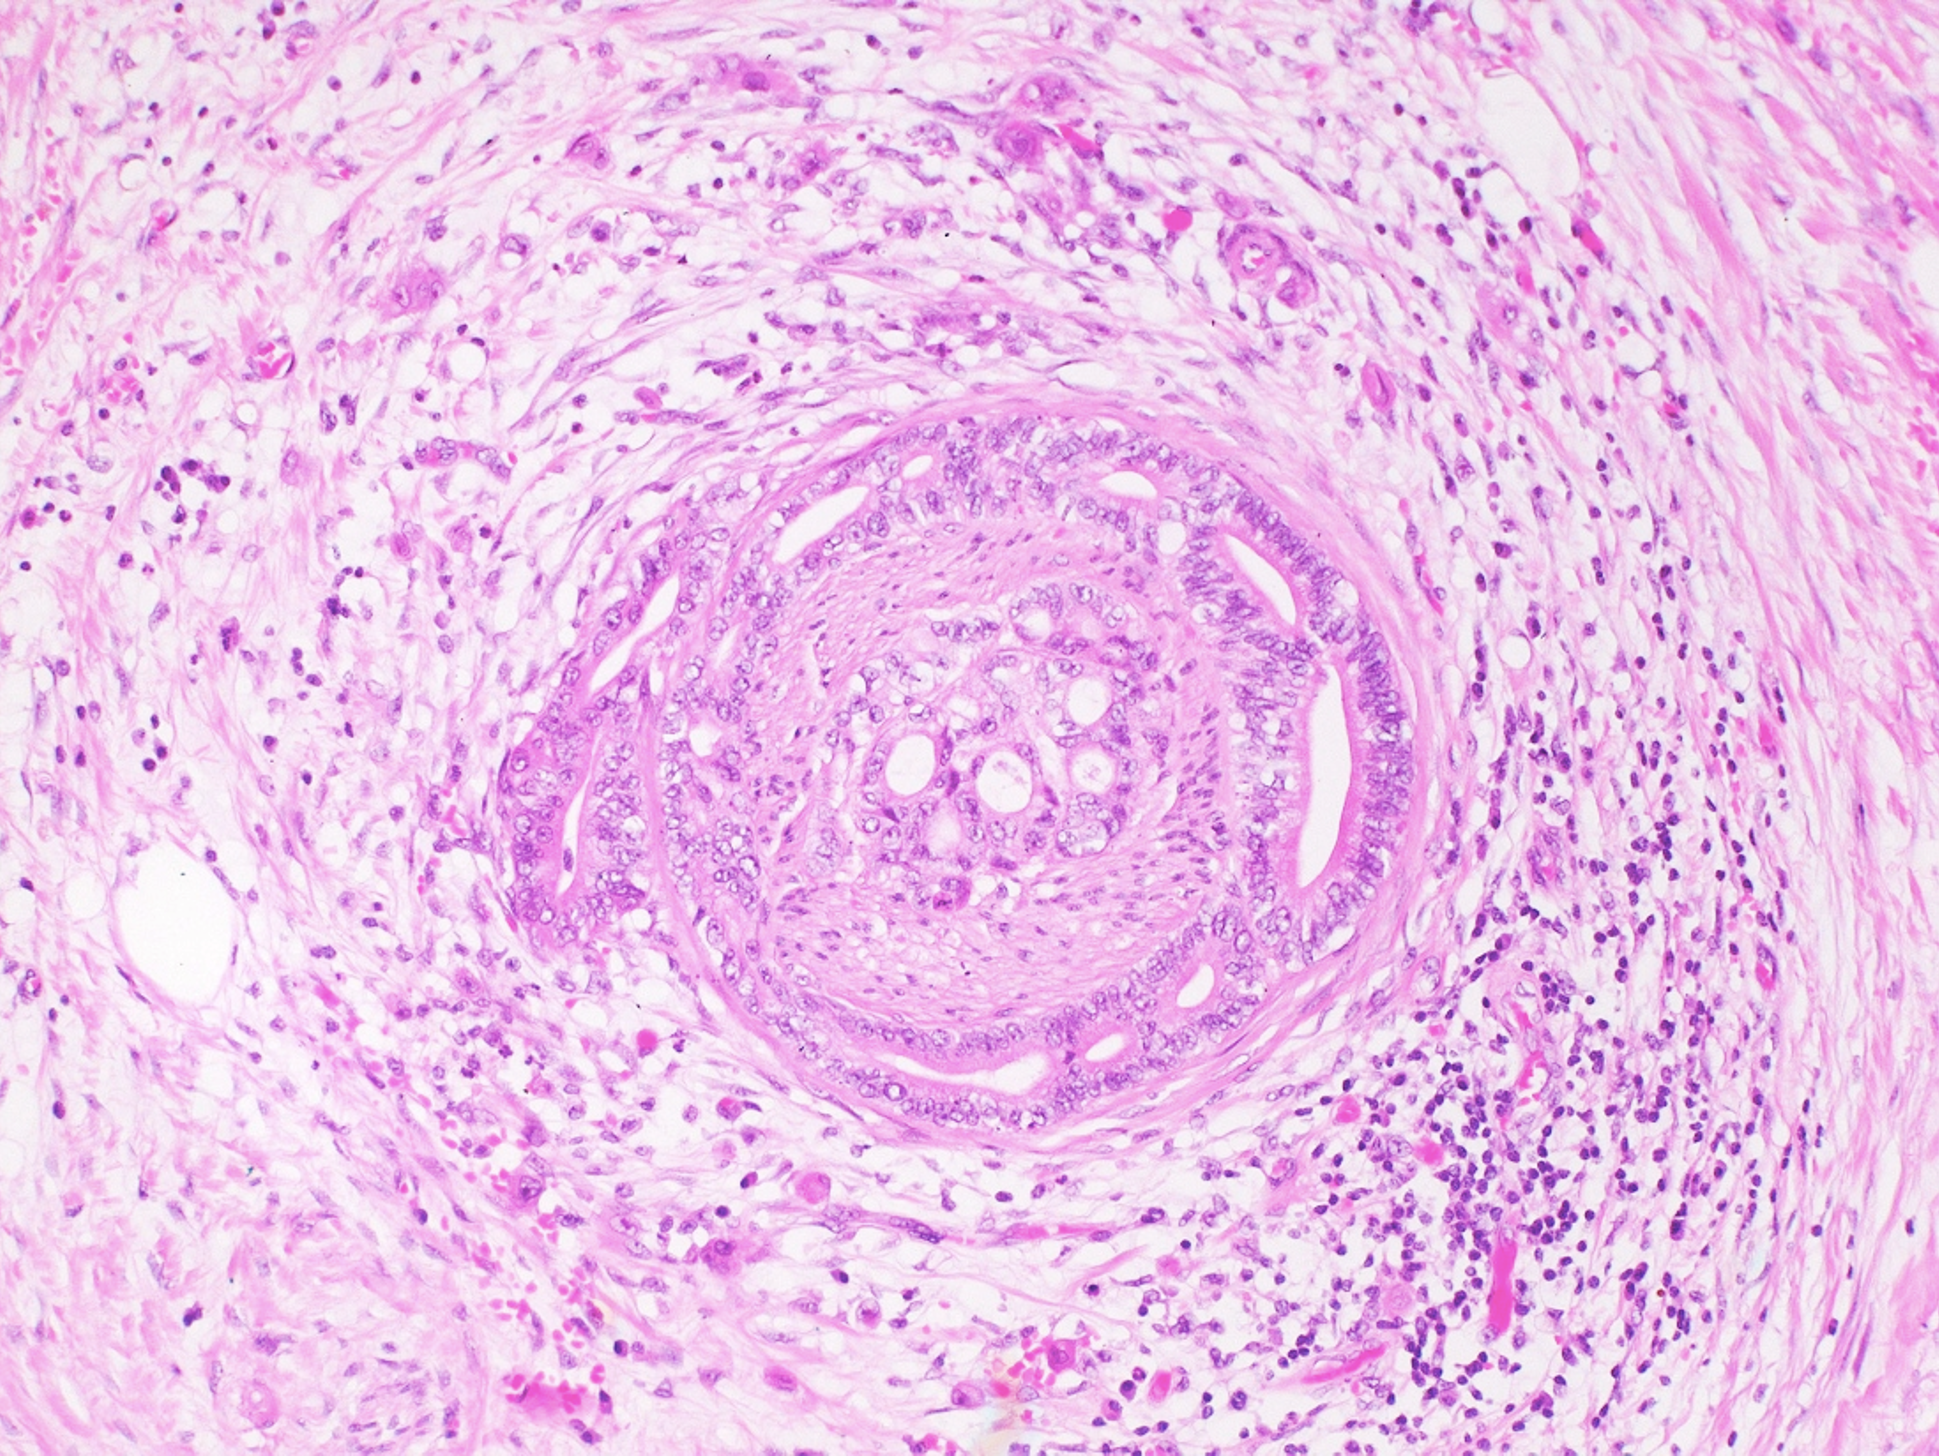

La pathologie est une discipline médicale à la fois fondamentale et clinique. Au sens strict, nous analysons des tissus, c'est-à-dire des biopsies ou des pièces opératoires, ainsi que des cellules – on parle respectivement d’examens histologiques ou cytologiques -, afin de poser un diagnostic aussi précis que possible à partir des lésions observées au microscope. Aujourd’hui, dans de nombreuses situations, nous complétons cette analyse par des techniques plus pointues, notamment en immunohistochimie et en biologie moléculaire, afin de préciser encore mieux le diagnostic et d’apporter des éléments supplémentaires pour la prise en charge thérapeutique.

Sur le plan organisationnel, nos laboratoires sont structurés en trois grands secteurs. Le premier regroupe la pathologie chirurgicale (histopathologie), qui prend en charge les échantillons tissulaires, fixés au formol ou à l’état frais. Après réception et enregistrement, la macroscopie permet d’examiner les pièces, d’identifier les zones d’intérêt et de réaliser des prélèvements ciblés représentatifs des lésions. Les échantillons sont ensuite pris en charge en histologie jusqu’à la production de lames, colorées puis numérisées avant lecture par les pathologistes. L’Institut de pathologie pratique également des autopsies dites « médicales », réalisées dans des contextes de décès non suspects. Elles permettent notamment de préciser la cause d’un décès inexpliqué, d’évaluer d’éventuelles complications liées à un traitement, ou encore d’identifier des malformations, des lésions ou certaines causes de décès in utero et périnataux.

Enfin, la pathologie moléculaire intervient en deuxième ligne pour des analyses complémentaires, avec trois laboratoires principaux, immunohistochimie, FISH et biologie moléculaire. À noter que nous disposons aussi d’un microscope électronique, indispensable pour certaines indications très spécialisées, notamment l’analyse des biopsies rénales.